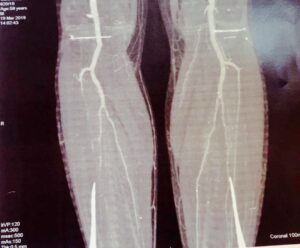

Шестиот ден се` се стабилизираше, забораваме на лошата епизода и полека почнувам да се грижам за десната нога на која двата прста и` помодреле. А, и цела нога малку атрофирала од лежење (онаа на која немам артерии од колено па надолу и прва алармираше). Но, кој гледа два прста кога за малку ќе ,,отидев”.

Ама…доаѓа утрината визита, ме откриваат и имаа што да видат. Повторно паника, брзо ,,доплер” на вени. И… сите вени на лева нога – запушени.

Ице полека заминува, а Христијан во следните два часа се појави со адвокат. Неколку думи, поделив што имам од овоземскиот свет наизуст, тој запиша и целиот разговор ми остана во глава дека ова тешко се оправа и дека нозете никогаш нема да ми бидат истите. Едната нога атрофирана и помодрена, другата бумбар отечена и венски непроодна.